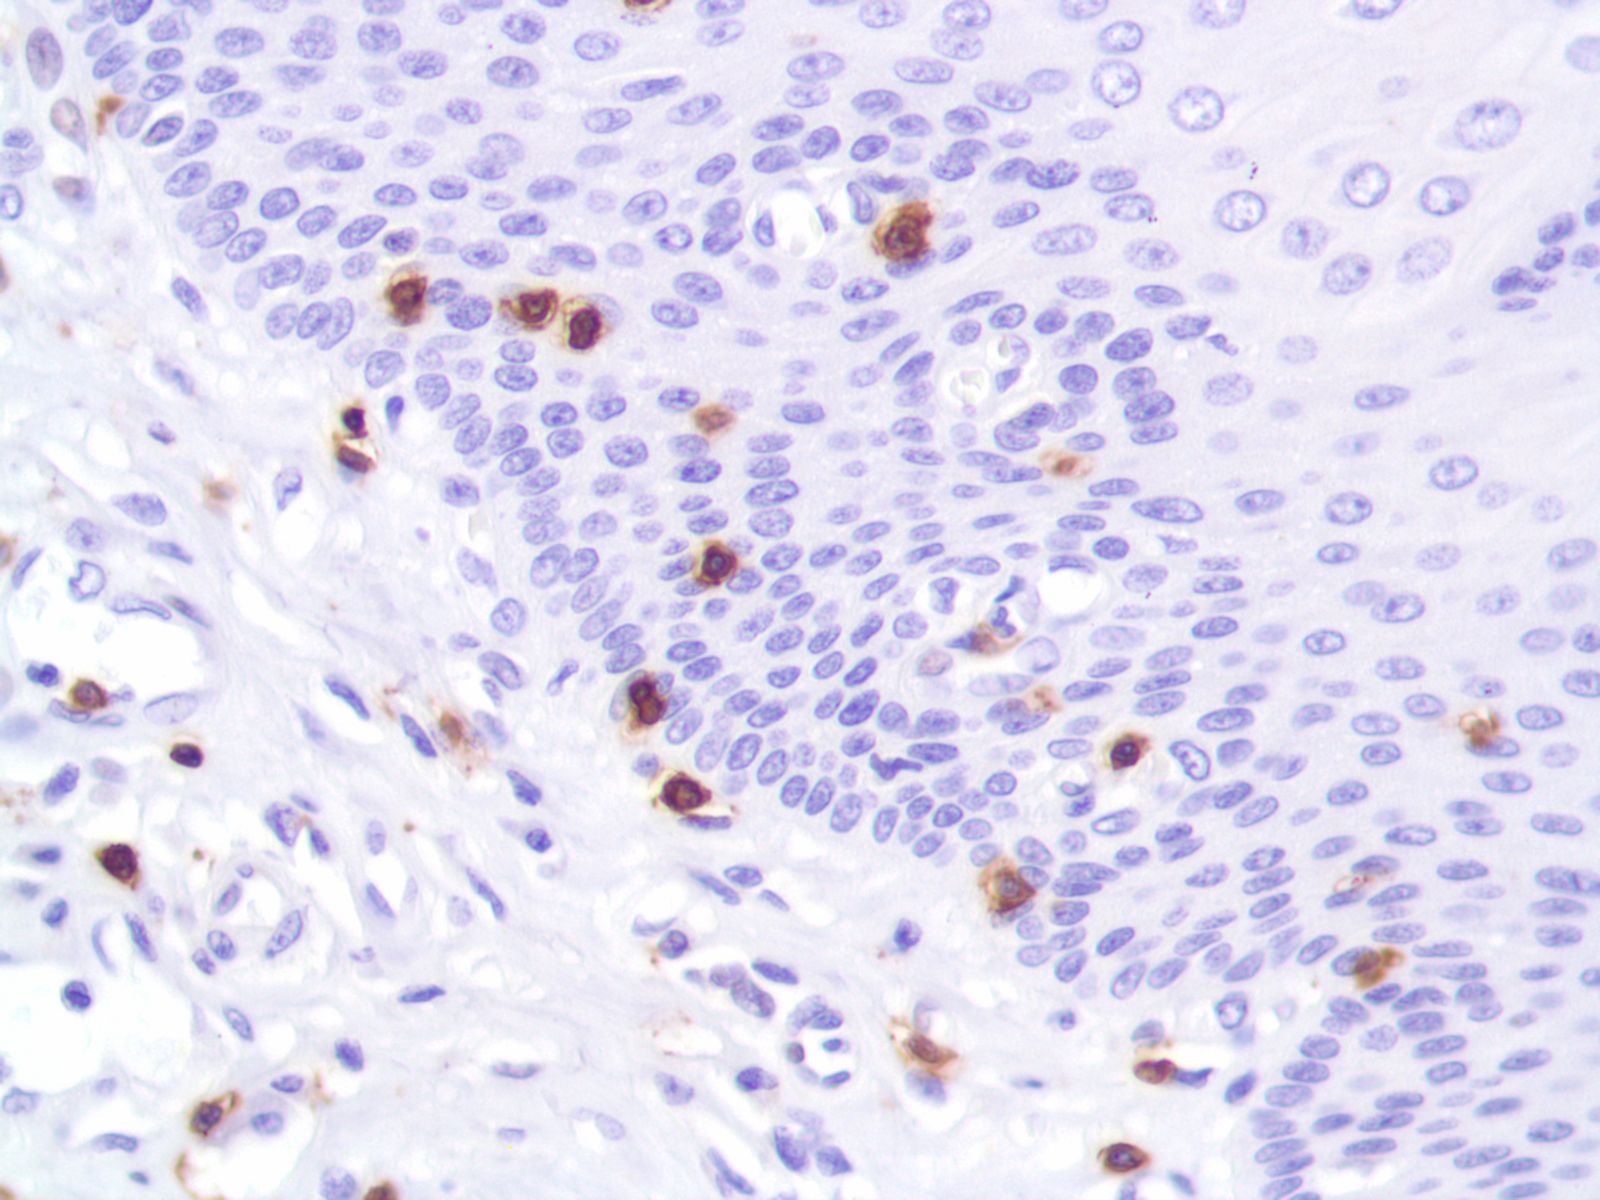

Микрофотографии гистологии глиобластомы головного мозга